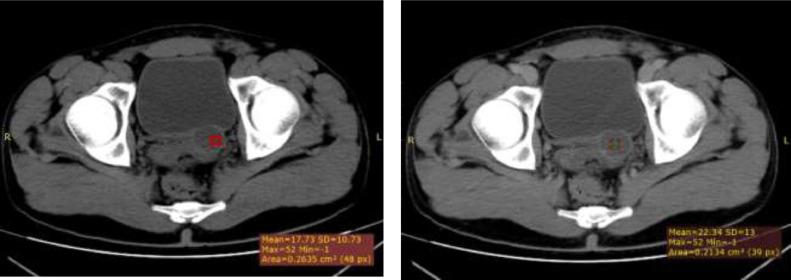

A triad of unilateral renal agenesis, ipsilateral seminal vesicle cyst and ipsilateral ejaculatory duct obstruction has been called Zinner syndrome since its first description in 1914 by Zinner. It is a very rare congenital abnormality of the male genitourinary tract due to abnormal embryologic development of the Wolffian ducts. There have been several case reports from different parts of the world about the clinical and imaging findings of these anomaly. In this case report, we present the first case report of Zinner syndrome in a 28-year-old male Ethiopian patient.

自1914年齐纳首次描述以来,单侧肾缺如、同侧精囊囊肿和同侧射精管梗阻三联征被称为齐纳综合征。它是一种非常罕见的男性生殖泌尿系统先天性异常,由中肾管胚胎发育异常引起。世界各地已有多篇关于这些异常的临床和影像学表现的病例报告。在本病例报告中,我们呈现了一名28岁埃塞俄比亚男性患者的齐纳综合征首例病例报告。